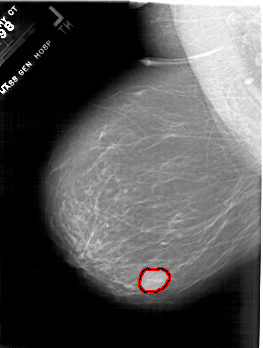

A_1801_1.LEFT_MLO

FILE: A_1801_1.LEFT_MLO.OVERLAY

TOTAL_ABNORMALITIES 1

ABNORMALITY 1

LESION_TYPE MASS SHAPE LOBULATED MARGINS CIRCUMSCRIBED

ASSESSMENT 4

SUBTLETY 5

PATHOLOGY BENIGN

TOTAL_OUTLINES 1

BOUNDARY